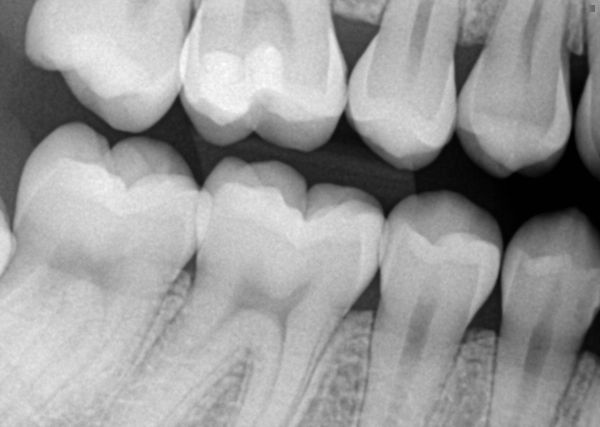

A radiologia odontológica digital oferece uma série de benefícios as pessoas e profissionais. Ela dispensa filmes radiográficos, oferece maior precisão em resultados, armazenamento de arquivos digitais com mais praticidade, que pode ser retirada através da internet ou por e-mail, menor exposição à radiação, e maior agilidade. Ao contrário da radiografia, que precisa ser revelada, a radiologia digital envia diretamente a imagem para o computador, deixando o processo de diagnóstico mais ágil, sem necessidade de esperar alguns dias para o exame ficar pronto.